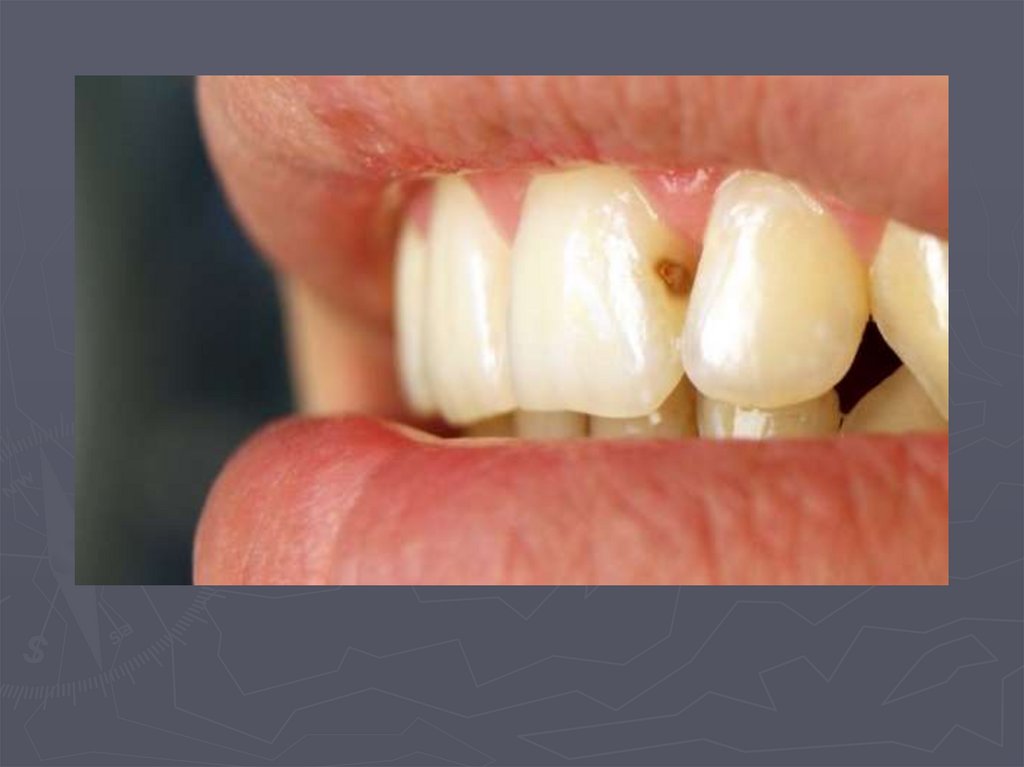

92. МЕТОДЫ ДИАГНОСТИКИ КАРИЕСА У ДЕТЕЙ

РЕНТГЕНОЛОГИЧЕСКИЙ МЕТОД –

применяется:

в случаях крайнего затруднения

диагностики,

► при локализации полостей на

апроксимальных поверхностях,

► при тесном положении зубов.

93. Кариес на рентгеновских снимках

94. Рентгенологическая классификация кариеса

95. МЕТОДЫ ДИАГНОСТИКИ КАРИЕСА У ДЕТЕЙ